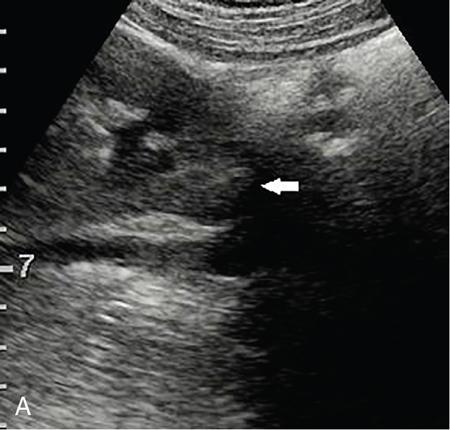

Drushi Patel CONTRAST-ENHANCED ULTRASOUND IN ADULT GENITOURINARY IMAGING Mridula Muthe Ultrasound is the initial screening examination for the evaluation of the renal morphology and suspected renal lesions due to its multiple advantages such as easy accessibility, bedside assessment, affordability and lack of radiation. Vascularity of the kidney and renal lesions can be studied with the use of colour Doppler ultrasound however, it provides information only about the macrovasculature. With the use of microbubble ultrasound contrast agents (UCAs) macro as well as the microvasculature can be studied. Contrast-enhanced ultrasonography (CEUS) is also more sensitive than Doppler ultrasound as it is not affected by blood velocity and angle of insonation of the ultrasound beam. In urology, the established applications of CEUS in adults include characterization of cystic lesions and differentiation between pseudotumours and solid lesions. Box 10.23.1.1 provides a list of European Federation of Societies for Ultrasound in Medicine and Biology (EFSUMB) recommended indications of CEUS in renal evaluation. EUROPEAN FEDERATION OF SOCIETIES FOR ULTRASOUND IN MEDICINE AND BIOLOGY (EFSUMB) RECOMMENDED INDICATIONS FOR USE OF UCA IN RENAL EVALUATION Renal ischaemia. Evaluation of solid renal lesions. Differentiation between solid renal lesions and pseudotumours. Characterization of complex cystic masses. Characterisation of indeterminate renal masses. Renal infections. Follow-up of nonsurgical complex masses. To improve lesion visualization in patients undergoing renal tumour ablation under US guidance and to detect residual tumour either immediately or after ablation. Isolated blunt moderate-energy renal trauma. Follow-up of trauma patients managed conservatively. Characterization of thrombus in renal vein and inferior vena cava. In patients with contraindications for CT- and MRI-based contrast media. Evaluation of lesions in transplant kidneys. Evaluation of ischaemia and vascular complications in transplant kidneys. Tumour response assessment to biologic therapy. Intracavitary CEUS for guiding percutaneous nephrostomy. Source: P.S. Sidhu, V. Cantisani, C.F. Dietrich, O.H. Gilja, A. Saftoiu, E. Bartels, et al., The EFSUMB guidelines and recommendations for the clinical practice of contrast-enhanced ultrasound (CEUS) in non-hepatic applications: update 2017 (long version). Ultraschall in der Medizin-Eur. J. Ultrasound 39 (02) (2018) e2–e44. CEUS involves the intravenous injection of UCAs consisting of gas microbubbles. These UCAs remain purely in the intravascular compartment as they are small enough to avoid filtration by the lungs and too large to enter the interstitial compartment. UCAs cause marked amplification of signals from the flowing blood, thus providing information about the microvasculature and parenchymal perfusion. Sonovue is a second-generation UCA and is the only UCA available in India. It consists of sulphur hexafluoride gas which is exhaled by the lungs and is surrounded by phospholipid monolayer which is metabolised by the liver, making it safe for patients with renal insufficiency. For renal evaluation, a dose of 1–1.5 mL of Sonovue is administered as a bolus dose followed by a 10 mL saline flush. CEUS is performed on machines with contrast-specific software’s using a low mechanical index (MI) technique. The use of a dual image display is beneficial for the evaluation of small lesions. A conventional B-mode ultrasound is first performed to acquire measurements, assess morphology and to detect focal lesions along with Doppler ultrasound to assess vasculature. However, due to limitations in the assessment of focal lesions, microvasculature, complex cysts, poor contrast between the lesion and cortex or medulla, it is preferable to perform a CEUS study for additional characterization. The enhancement pattern of the kidney is different than that of the liver due to the dual blood supply of the liver as opposed to afferent arterial supply and efferent venous drainage of the kidney. After an intravenous bolus of UCA, kidneys show intense enhancement. Contrast is first seen in the main renal artery, followed by its branches. CEUS has only two enhancement phases, that is cortical phase which lasts for 15–30 seconds and a parenchymal phase (enhancement of both cortex and medulla) for 25 seconds–4 minutes after UCA administration. The renal cortex enhances first, followed by the outer medulla which is followed by gradual enhancement of the pyramids (Fig. 10.23.1.1). During the washout phase first, there is a reduction in the medullary enhancement followed by a slower washout of the cortex. As kidneys don’t excrete UCAs, there is no opacification of the pelvicalyceal system. UCAs can act as a problem-solving tool in patients with renal failure as they are not nephrotoxic. Due to its excellent ability to depict renal vascularization, it can be used for detecting perfusion abnormalities. CEUS is useful for detecting vascular causes of renal function deterioration. Renal infarcts appear as wedge-shaped nonenhancing areas in all phases. Renal infarcts show a focal complete lack of parenchymal enhancement on CEUS whereas ischaemic areas show reduced enhancement. CEUS can confidently differentiate infarction from cortical necrosis by the demonstration of preserved hilar vascularity in the latter. Renal pseudotumours such as foetal lobulations, dromedary hump, parenchymal hypertrophy due to renal scarring and column of Bertini can be accurately differentiated from true tumours using CEUS. Pseudotumours show similar enhancement to the adjacent parenchyma and appear isoechoic on all phases while true tumours show different enhancement pattern on at least one phase (Fig. 10.23.1.2). True tumours will cause mass effect and distort the normal vascular architecture of the renal parenchyma whereas in pseudotumours the vascular architecture is preserved. In addition, the identification of medullary pyramids within the mass points towards it being a pseudotumour rather than a true mass. Cysts can be categorized according to the Bosniak classification using CEUS. Due to its superior spatial and temporal resolution, CEUS is considered superior to CT for detecting additional septations, wall or septal thickening and solid components (Figs 10.23.1.3–10.23.1.5). CEUS allows for real-time imaging of blood flow within the septae, wall or nodules within the cysts which may not be seen on CT or MR imaging. The sensitivity of CEUS is comparable to CT for the classification of renal cystic lesions as benign or malignant however, it is not as useful for staging. The follow-up of inoperable complex cystic lesions is better performed with CEUS rather than CT due to the absence of ionizing radiation. Complex cysts or masses with calcifications are not suitable for evaluation with CEUS. CEUS allows a detailed evaluation of the circulation in mass lesions as it demonstrates the macro as well as microvascular enhancement patterns. CEUS has more sensitivity than CT for detecting blood flow in hypovascular lesions. It can also be used to distinguish between complex cysts and solid lesions which remain equivocal on CT and ultrasound (B-mode and colour Doppler). CEUS is sensitive in identifying cystic areas, necrosis, debris and haemorrhage in small tumours that may be difficult to visualize on CECT and MR. Isoechoic lesions on conventional ultrasound are better characterized by CEUS (Fig. 10.23.1.6). Hyperdense renal lesions on noncontrast CT (NCCT) with HU values between 20 and 70 are better evaluated by CEUS which can classify these lesions as solid or cystic. CEUS can suggest the histological subtype of tumours. Clear cell carcinomas show heterogeneous hyperenhancement in the cortical phase and rapid washout along with a peripheral enhancing rim or pseudocapsule seen during the parenchymal phase. Papillary carcinoma shows progressive heterogeneous enhancement during the cortical phase and displays hypoenhancement as compared to the cortex on all phases. Malignant renal vein thrombus will show enhancement as compared to bland thrombus on CEUS. Tumours that are smaller than 3 cm commonly show homogeneous enhancement, regardless of their histologic subtype. Differentiation between angiomyolipoma, renal cell carcinoma and oncocytoma is not always possible. Although, CEUS has excellent sensitivity for the detection of malignancy, it has a higher false-positive rate as compared to CECT. Hence, combined use of CEUS for its high sensitivity and CECT for its high specificity may be performed for an accurate diagnosis. CEUS is effective in patients with complicated pyelonephritis, for identifying inflammatory parenchymal involvement, characterized by round or wedge-shaped hypovascular parenchymal areas, most conspicuous during the late parenchymal enhancement phase. An abscess is seen as a nonenhancing area, with or without peripheral or septal enhancement. CEUS can also be used for the follow-up of renal abscesses. All the aforementioned indications of CEUS in native kidneys also apply to renal transplants. Infarction, vascular complications such as arterial and venous thrombosis can be detected. Quantitative CEUS for assessment of graft dysfunction is a subject of active research. CEUS can be used as an alternative to CT especially in children with isolated blunt moderate energy injuries who are hemodynamically stable. It can also be used in the follow-up of conservatively managed trauma patients and in renal impairment. During Focused Assessment with Sonography for Trauma (FAST), the examination should begin with the kidneys as they have a fleeting enhancement. The kidneys are studied in the arterial phase with two separate doses administered for either kidney during FAST. On CEUS, lacerations, hematomas, and infarcts are seen as nonenhancing areas on late-phase images whereas contusions may show faint enhancement. Pseudoaneurysms and active bleeding are diagnosed on the arterial phase. Crucial complications such as devascularized parenchyma and acute cortical necrosis can also be diagnosed on CEUS. Pelvicalyceal system injury cannot be detected by CEUS as UCAs are not excreted by the kidneys. CEUS can be performed in conjunction with percutaneous ablation therapies. Preablation evaluation with CEUS is essential to assess lesion vascularity and to compare pre and postprocedure tumour viability. Also, the identification of a pseudocapsule predicts improved ablation efficacy. CEUS has demonstrated high sensitivity, specificity and accuracy for the early detection of residual unablated tumour. Dynamic contrast-enhanced ultrasound is a useful tool for early identification of responders and nonresponders, enabling tailoring of the treatment regimen. It is performed by two methods – Bolus injection of a UCA with time-intensity curve analysis (commonly used) and intravenous injection of UCA with disruption–replenishment analysis. In patients with chronic kidney disease, the contrast enhancement is less intense and fades earlier as compared to a normal kidney. CEUS aids in characterizing renal lesions in patients with renal failure. Characterization of lesions with indeterminate appearances in patients with renal dysfunction, on conventional US prevents unnecessary further evaluation with contrast-enhanced CT or MRI and further deterioration of the renal function as well as unwarranted investigations. CEUS nephrostomogram can be performed after percutaneous nephrostomography to confirm the correct positioning of its tip, detect the site of obstruction and to diagnose complications. UCAs can be safely administered in patients with minimal risk. They can be safely administered in patients with renal insufficiency as they are not excreted by the kidneys. Prior laboratory tests are not indicated as they are not nephrotoxic and don’t interact with thyroid function. Most adverse effects are mild such as nausea, headache, chest discomfort, chest pain and resolve spontaneously. The contraindications include known hypersensitivity, patients with right-to-left shunts, severe pulmonary arterial hypertension (pulmonary arterial pressure >90 mm Hg), uncontrolled systemic hypertension, and respiratory distress. The rate of anaphylactic reactions is significantly lower than iodinated contrast media and comparable to gadolinium-based contrast agents. Caution should be exercised in patients with severe acute coronary disease and in patients with unstable angina. CEUS is a rapidly evolving technique, can be conveniently performed as an extension of conventional ultrasound and acts as a valuable tool in the characterization of indeterminate renal lesions, especially when the lesion is small. The advantages of CEUS include quick assessment, real-time imaging, high contrast resolution, excellent safety profile, lack of ionizing radiation, great repeatability, and most importantly, ideal for contrast evaluation in patients with deranged renal function. DUAL-ENERGY AND SPECTRAL IMAGING IN GENITOURINARY SYSTEM Aditi Chaitanya Gujarathi-Saraf Dual-energy CT (DECT) also known as ‘spectral imaging’, was first conceptualized in the 1970s. However, the clinical applications of DECT have recently emerged as owing to improvements in postprocessing techniques. The development of a single-detector, single-source DECT (ssDECT) with the capability for rapid alternation between two peak voltage settings (‘fast switching’) and a dual-detector, dual-source DECT (dsDECT) system in last few years have made possible various applications in solving clinical problems. In DECT, the simultaneous use of two different X-ray beam energy settings (80 and 140 kVp) allows the differentiation of materials on the basis of their attenuation characteristics (material density). There are two major applications of DECT in genitourinary system. First being characterization of renal calculi to differentiate those containing uric acid (UA) from those which do not. The other application is to characterize small renal masses which include differentiating complex cysts from renal tumours, detection of solid growth in PCKD patients and detection of residual tumour after thermal ablation of a renal neoplasm. The principle of DECT imaging is based on the differential absorption of X-ray energy at variable kVp settings. In DECT, two energy levels (typically 80 and 140 kVp) are used to acquire images that can be processed to generate additional datasets. Thus, a tissue or any material in the body shows different degrees of attenuation when scanned at different X-ray energies. Conventional CT numbers (attenuation measurements in Hounsfield units) are related to the linear attenuation coefficient of a particular material. The unique linear attenuation coefficients obtained by imaging at two different energies can be used to discriminate between different materials (e.g. fat, calcium, iodine and water). The characterization of material on DECT depends on their CT number ratio (CTR) also called dual-energy ratio. DE RATIO = CT number of a given material in the low-energy image CT number of the same material in the high-energy image DECT and spectral CT can be performed by three techniques (Fig. 10.23.2.1): Two sets of material-specific images are created to detect the presence or absence of a material. The two basic materials selected should have significant difference in mass attenuation coefficients and atomic number. The two commonly selected pairs are: Iodine-specific images are most commonly used in the clinical practice. When iodine is paired with water, two separate image data sets are generated. On water density image, the voxels that show change in attenuation due to presence of iodine are removed. These are instead represented on iodine density images. Thus, virtual unenhanced images are generated which resemble the conventional unenhanced images. Renal calculus disease is a common disease affecting approximately 10%–14% of population in India commonly affecting 31–45-year-old patients. Accurate diagnosis of composition of renal calculi is crucial as the frequency of prevalence and recurrence rate of renal calculi is high in most states of India. The obstructing calculi can lead to obstructive uropathy, pyelonephritis, urinary sepsis with nearly 50% of the patients being affected by renal failure. There are multiple compositions of renal calculi, most common being calcium oxalate (70%), calcium phosphate (20%), uric acid (8%) and cystine (2%). In general, UA calculi have lower attenuation values than nonuric acid calculi (i.e. struvite, cystine and calcium) on conventional CT. However, it may be difficult to distinguish between the two due to overlap in attenuation values. Here DECT becomes a problem-solving tool as it uses the two-material differentiation approach. Thus, in addition to size and location, DECT provides information about the composition of calculi to the urologist. DECT has high sensitivity of 88%–100% and high accuracy of 93%–100% to differentiate UA calculi from nonuric acid UA calculi. This is of utmost clinical importance as UA calculi can be treated medically whereas non-UA calculi require invasive methods of treatment such as extracorporeal shockwave lithotripsy (ESWL) or percutaneous nephrolithotripsy (PCNL). In clinical practice, NCCT scan of KUB region is performed at 80 and 140 kVp to generate two image datasets and obtain the DE ratio. A cut-off value of DE ratio of 1.2 is used to differentiate UA calculi from non-UA calculi (Fig. 10.23.2.2). Following flow chart shows differentiation of renal calculi based on DE ratio.